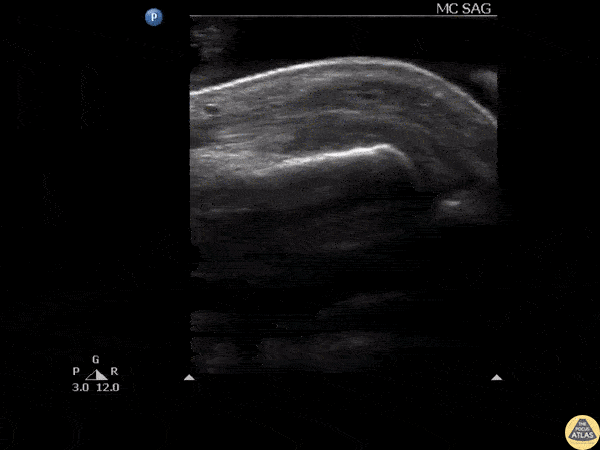

Soft Tissue - Glass FB in Extensor Tendon

Ultrasound clip reveals a shard of glass broken off and lodged in the extensor tendon over an MCP joint. Image courtesy of Robert Jones DO, FACEP @RJonesSonoEM Director, Emergency Ultrasound; MetroHealth Medical Center; Professor, Case Western Reserve Medical School, Cleveland, OH View his original post here